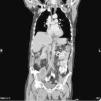

Common and applicable diagnostic methods are available for brucellosis. However, its life-threatening complications remain critical. Herein we present a 68-year-old patient who complained of leg pain for two months. At admission he had absent pulse in the left femoral and bilateral popliteal arteries. Laboratory test results were leucocytes 8700/mm3, CRP 86mg/L, and ESR 47mm/h. Abdominal CT revealed images consistent with mural thrombus in the suprarenal segment of abdominal aorta, total occlusion and hypodense thrombus material completely filling the aortic lumen through infrarenal segment extending to lumens of the caudal, bilateral common and superior iliac arteries (Figs. 1–3). No paleness, coldness or color change was detected in the lower extremities. The patient had fever, right inguinal swelling, and sweating. Abdominal CT showed an aortic thrombus and a hypodense lesion of 58mm×61mm×100mm in the right psoas muscle. The repeated Brucella STA test was positive in 1:5120 titer. USG-guided drainage of the psoas abscess was performed and a treatment with doxycycline and rifampicin was administered for three months (Fig. 4). The patient was not operated on and progressed with no clinical complaints.